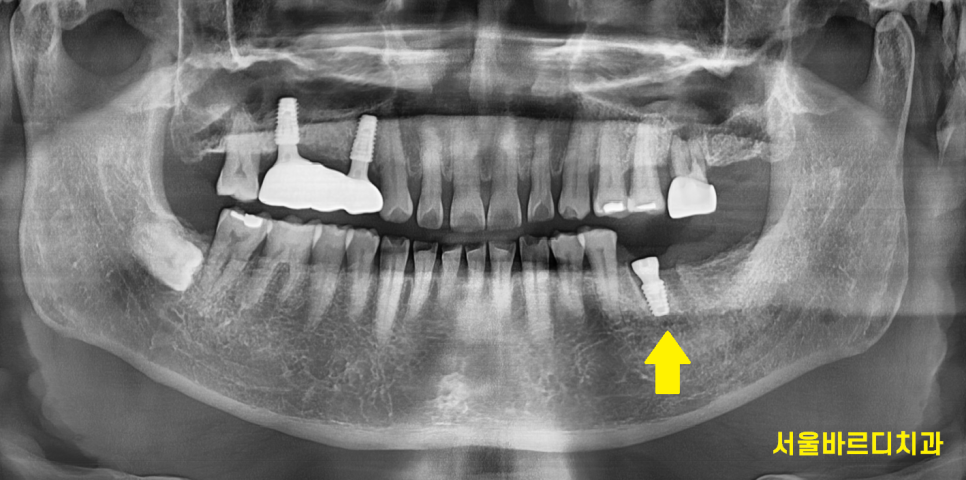

240430

오늘의 환자분도 신경치료 후 통증으로 고생하시다가

발치 후 강일역 임플란트 진행했습니다.

240905 강일역 임플란트 결과